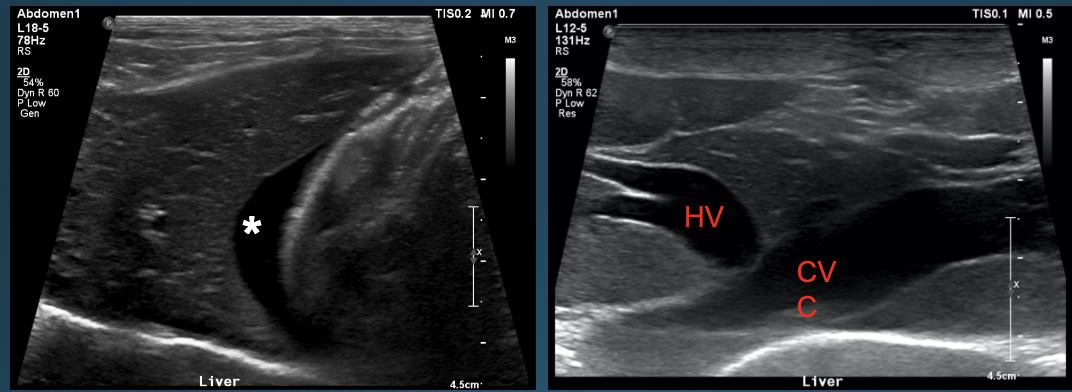

What is shown in these images?

normal ultrasound of the liver